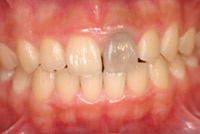

治療後

![]() |

歯はまったく削ってません。